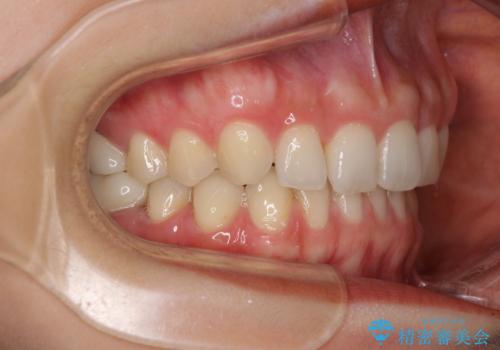

- 前歯の隙間と奥歯の目立つ銀歯を気にして来院された患者様です。

インビザラインにより下顎前歯の隙間を閉じるとともに、奥歯の咬み合わせを改善させることとしました。

矯正治療後には、銀歯のクラウンをセラミッククラウンへ替える補綴治療を行うこととしました。